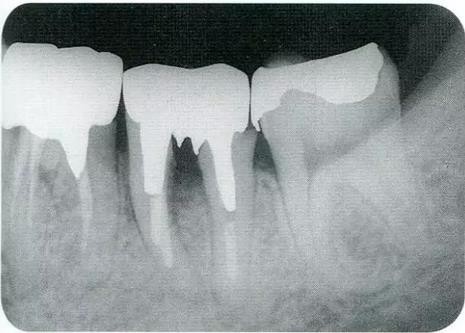

▼圖19-1

圖19-1 未超過冠寬1/3的分叉部病變(II度),通過備牙改善食物的流向,形成便于清潔的形態(tài)。

▼圖19-2

圖19-2 分叉部病變超過冠寬1/3,即使進(jìn)行備牙也很難得到便于清潔的形態(tài),如果超過1/2的話,就不可能通過備牙來改變。這是就需要使用牙根分割進(jìn)行治療。

▼圖19-3

圖19-3 這種情況下,無法通過備牙進(jìn)行清潔,需要進(jìn)行分割。